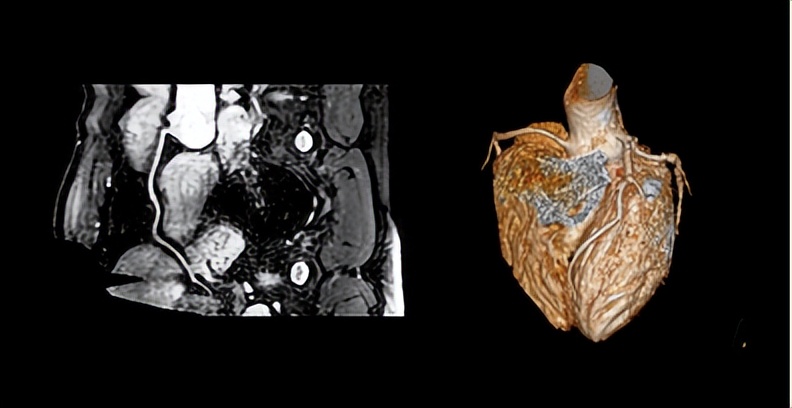

◆ 1分钟肿瘤筛查新模式: 类PET成像在肿瘤筛查、疗效随访等方面具有重要价值。Elition光影磁共振类PET成像每站不到20s,仅需1分多钟即可完成,而传统磁共振类PET成像往往需要10分钟左右的时间。Elition光影磁共振显著提高了类PET成像的效率,进一步促进类PET成像在临床的广泛应用。

◆ 1分钟无创冠脉早筛新模式: 突破性的零涡流梯度独家实现极速的18s不打药3D冠脉,将传统需要10分钟甚至更长时间的全心冠脉实现秒级的突破,让全心冠脉成像从科研走向临床,助力无创冠脉早筛成为现实。